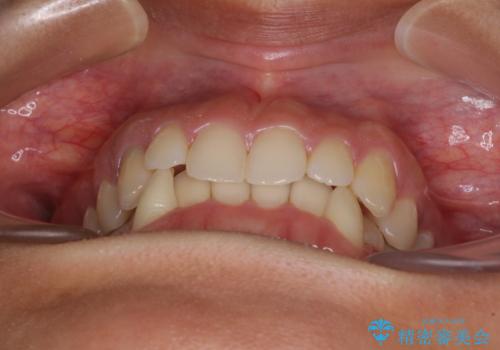

- 下顎の八重歯を気にして来院された患者様です。

下顎前歯にデコボコが集中していたため、顎間ゴムによる後方移動とIPR(歯と歯の間を削ること)により歯列を整えることとしました。